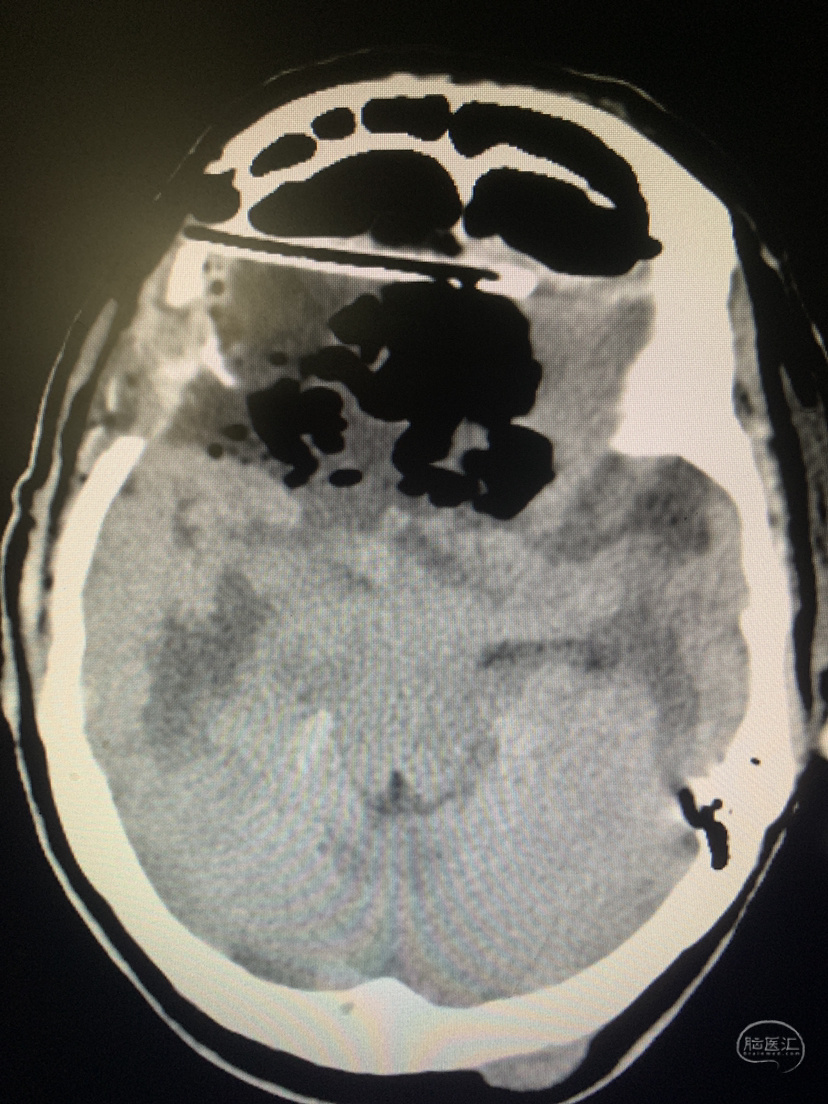

双侧入路计划(为降低优势半球损伤风险先右侧处理,实在不好搞再左侧)

从右额分块切除处理大部分后,因条件所限单侧入路风险高遂加开左侧额外侧(骨窗较右侧小)。

术前术后对比

术后CT